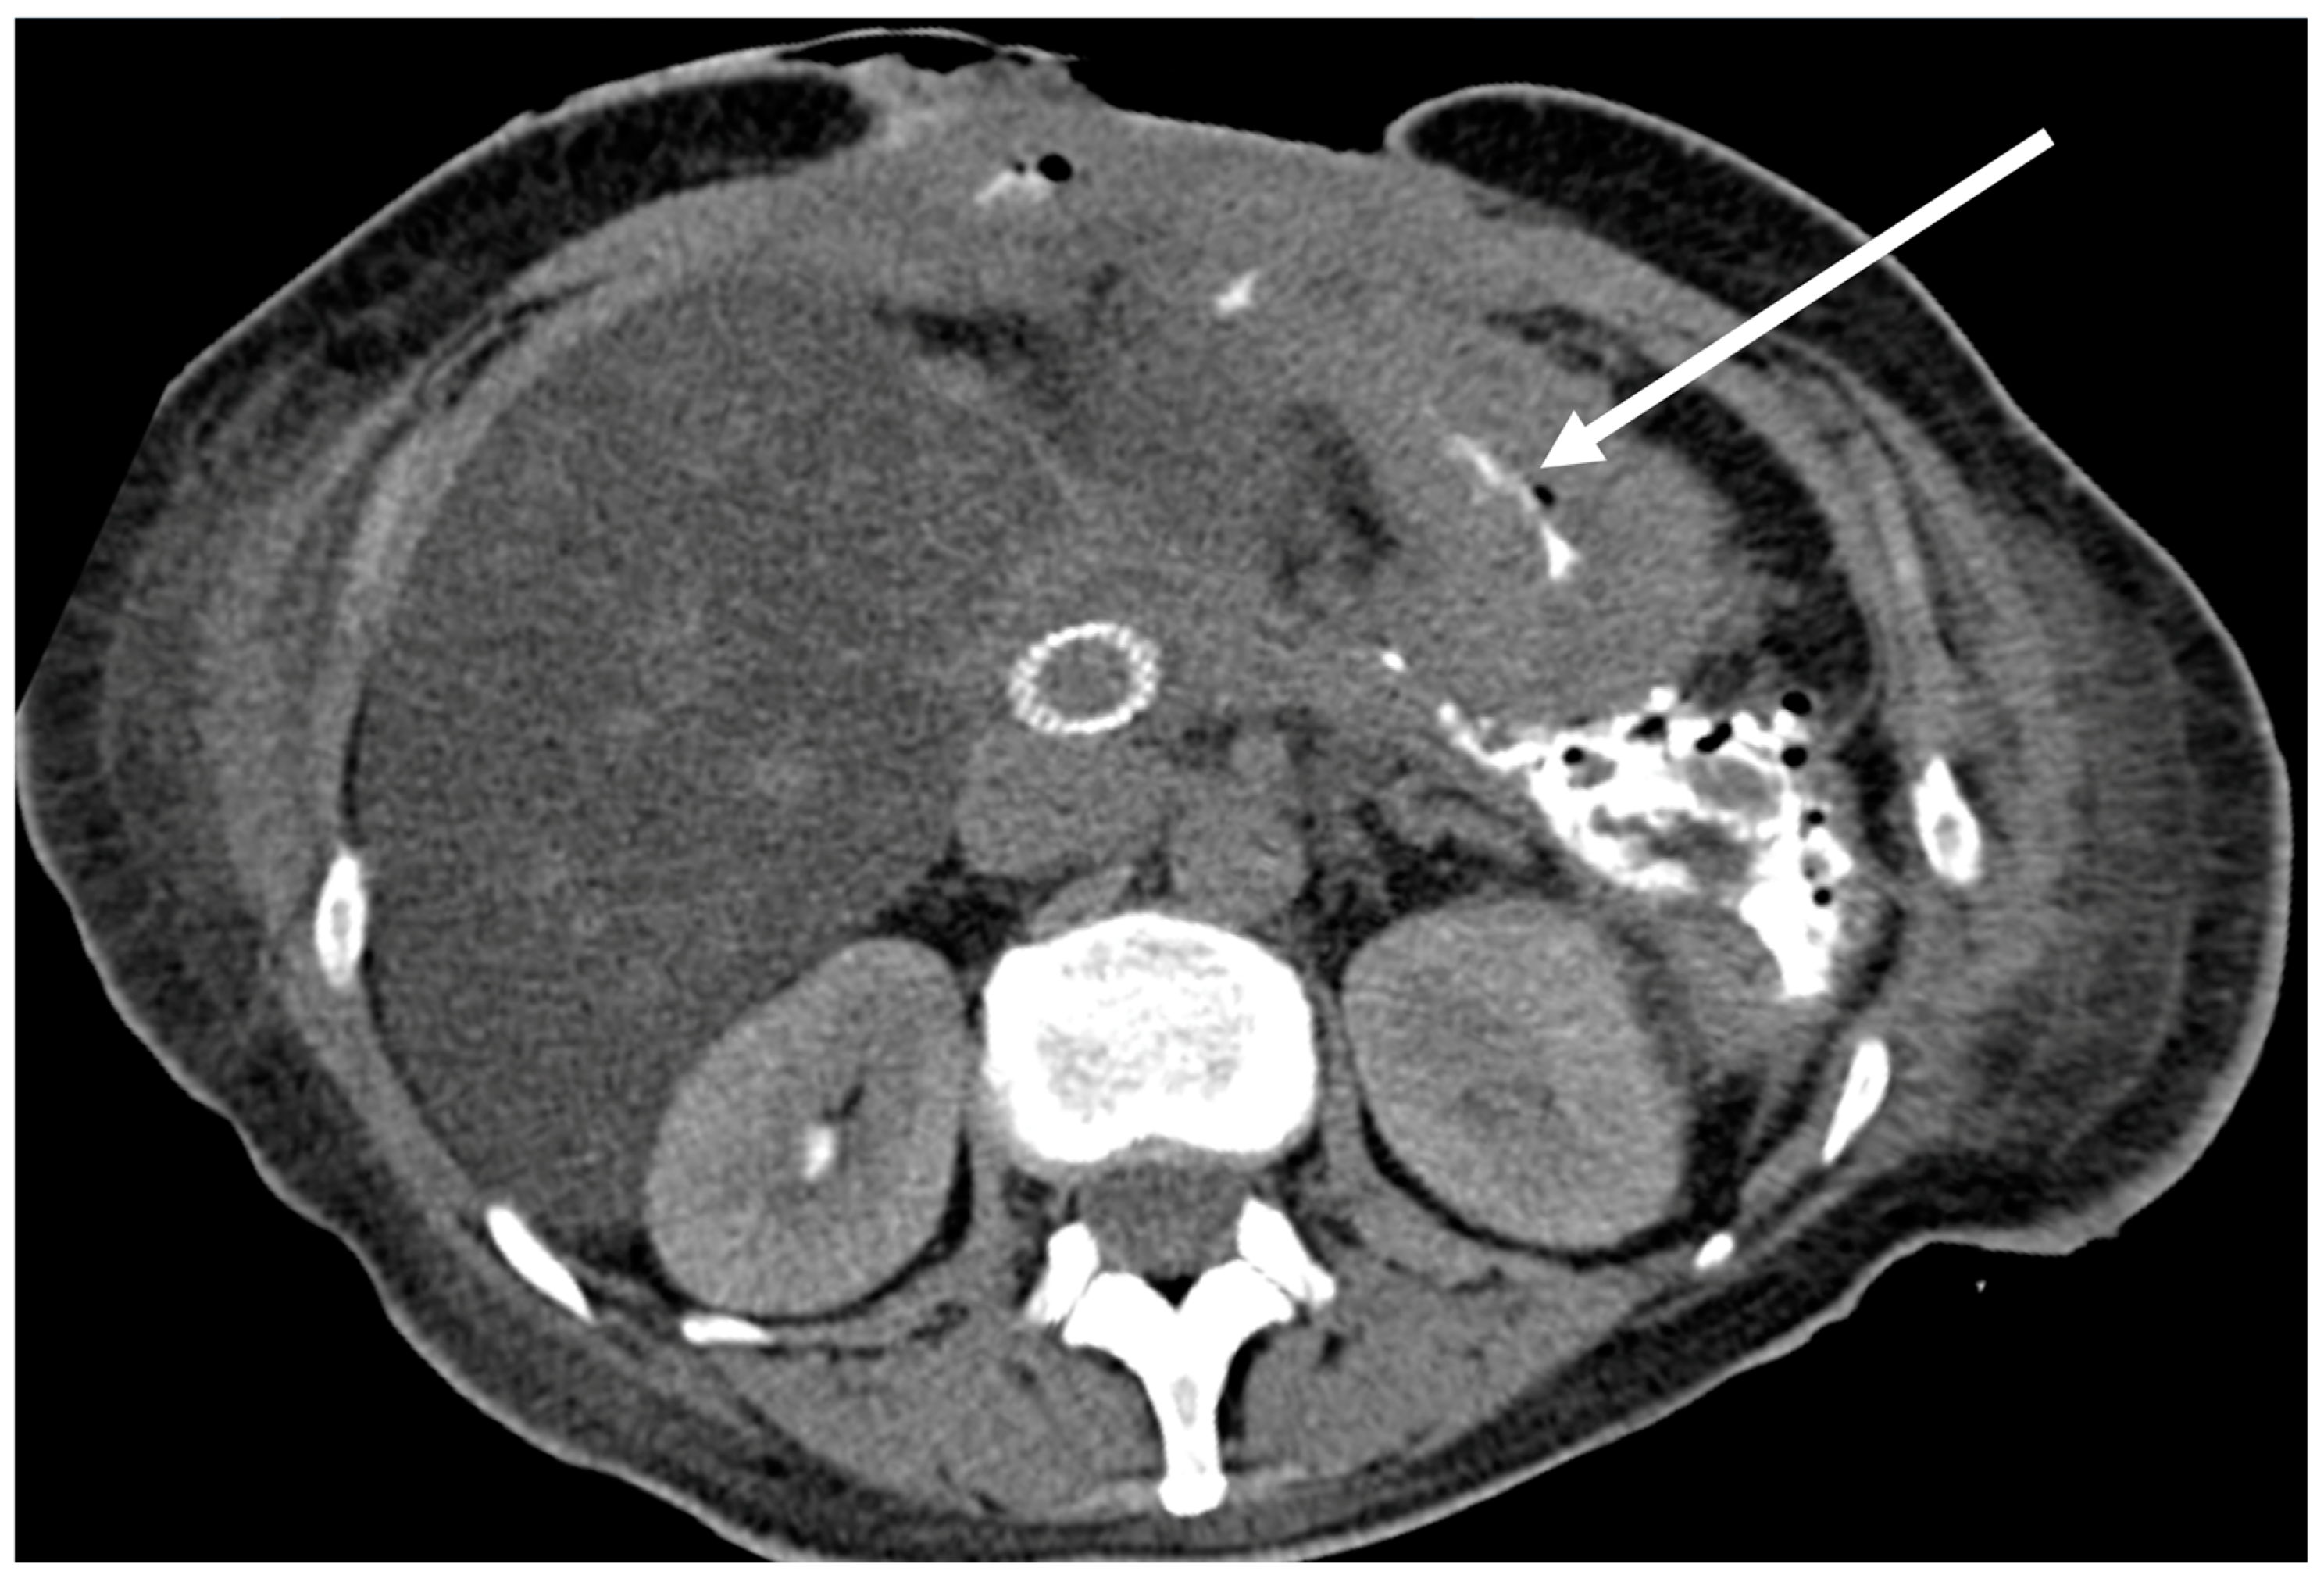

| Fistulas | 22 | 11 | 11 |

| Descending psoas abscess | 1 | 0 | 1 |

| Contact with aortic prosthesis | 1 | 0 | 1 |